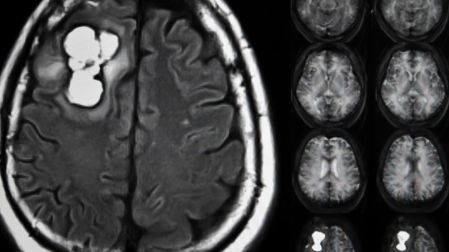

Fármaco para hipertensión detiene crecimiento de cáncer cerebral

Un fármaco clásico para la hipertensión bloquea la enzima ADO y frena el crecimiento de tumores cerebrales agresivos, según un estudio de la University of Pennsylvania.

La investigación, liderada por el laboratorio de Megan Matthews en la University of Pennsylvania y publicada en la revista Science Advances, revela cómo el fármaco antihipertensivo Hidralazina actúa sobre la enzima sensora de oxígeno ADO.

En el experimento, trataron células de Glioblastoma humano con hidralazina; al tercer día, las células dejaron de dividirse y entraron en un estado de senescencia —es decir, pararon su proliferación sin morir inmediatamente—.

La publicación de la University of Pennsylvania presenta datos in vitro que demuestran el efecto de la hidralazina sobre células de glioblastoma: bloqueo de ADO, inducción de senescencia, detención de la proliferación tumoral.